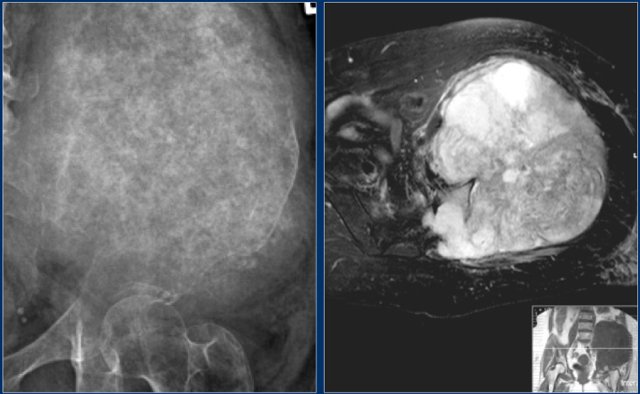

Here a chondrosarcoma of the left iliac bone.

Because of the large dimensions with soft tissue extension on plain radiograph and axial T2-weighted MR image, a high grade chondrosarcoma was suspected.

Biopsy showed grade 2 chondroarcoma.

Continue with the bone scan.

Intense uptake on bone scintigraphy as we would expect in high grade chondrosarcoma.